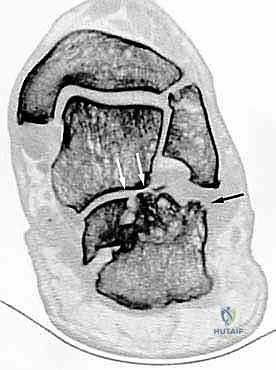

- الأشعة المقطعية ثلاثية الأبعاد (3D CT Scan): وهي الخطوة الذهبية والأهم في عيادة الدكتور هطيف. تتيح هذه الأشعة بناء نموذج ثلاثي الأبعاد دقيق للكعب المشوه، مما يسمح بتحديد أماكن الانحشار العظمي بدقة المليمتر، ومعرفة مدى تلف الأسطح المفصلية. بناءً على هذه الصور، يتم وضع خطة "القطع العظمي التصحيحي" قبل دخول غرفة العمليات.

- دمج المفصل تحت الكاحل (Subtalar Arthrodesis):

في الغالبية العظمى من حالات سوء الالتئام، يكون المفصل تحت الكاحل قد تدمر تماماً بسبب الخشونة والاحتكاك. الحل الجذري والنهائي للألم هنا هو "دمج" أو "تثبيت" هذا المفصل. يقوم الدكتور هطيف بتنظيف الغضاريف التالفة بالكامل، ووضع العظام في وضعها التشريحي الصحيح، ثم تثبيتها باستخدام براغي معدنية قوية جداً (Screws) لتلتحم وتصبح عظمة واحدة صلبة خالية من الألم.